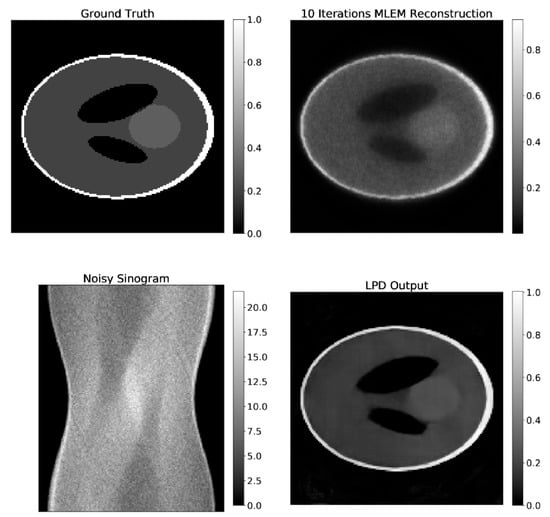

3.1. Results on Synthetic Data